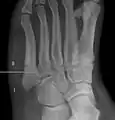

לסיבות שונות, שבר ג'ונס עלול לא להתאחה מכיוון שהדיאפיזה (גוף העצם), האזור שבו מתרחש השבר (אזור II), הוא אזור שאספקת הדם בו מעוטה. בנוסף, ישנם גידים שונים, כמו השריר השוקיתי הקצר, השריר השוקיתי השלישי ושני השרירים המחוברים לעצם שעלולים למשוך את שני צדדי השבר ולמנוע אותו מלהתאחה.

החיבור בין האזורים I ו-III הוא אמנם יחסית חזק, אך הוא מגביל את התנועה בצורה מעוטה. מצד שני, אזור II השני אינו מחובר באופן חזק, וכתוצאה מכך, ישנה הסכמה כללית ששברים באזור זה נחשבים כסוג של אימוביליזציה פנימית.

הבחנה בין אזורים אלה הוא דבר חשוב מבחינה קלינית, וניתן לעשות אותו באופן אנטומי וגם באמצעות קרני רנטגן.[9] לעיתים התערבות כירורגית כרוכה בסיבוכים, ולא תמיד מובילה להחלמת והתאחות השבר. דעות שמרניות, מעדיפות טיפול ללא ניתוח בשברי ג'ונס אצל אנשים שאינם ספורטאים.[10]

- שלושה אזורים מתוארים

- שני אזורים מתוארים